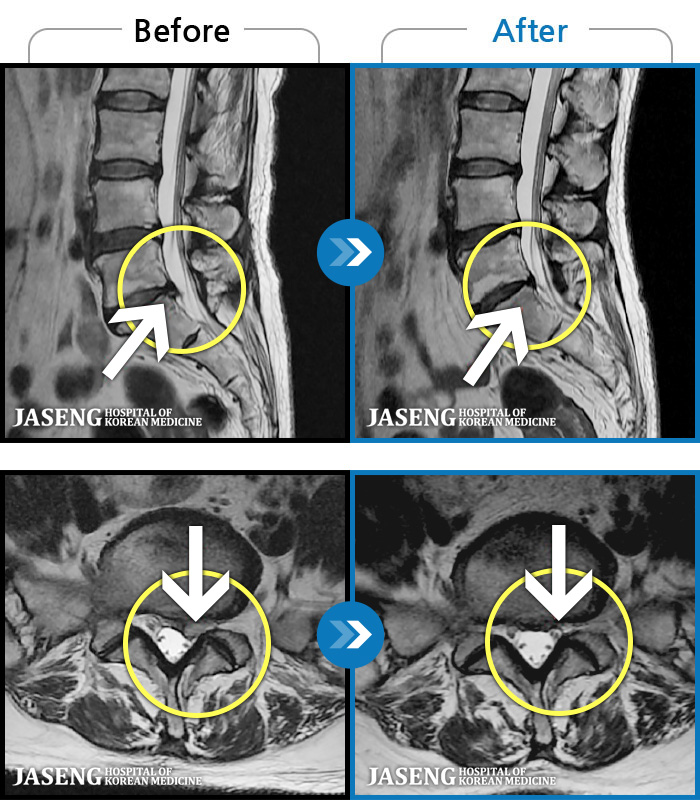

허리디스크

대전 · 김창연 원장

허리통증이라 왼쪽 발목~발등이 저려요. 엄지발가락에 힘빠지는 느낌, 전기오는 느낌이 있어요.

촬영시기

2023.07.17 ~ 2024.07.26

2024.08.09